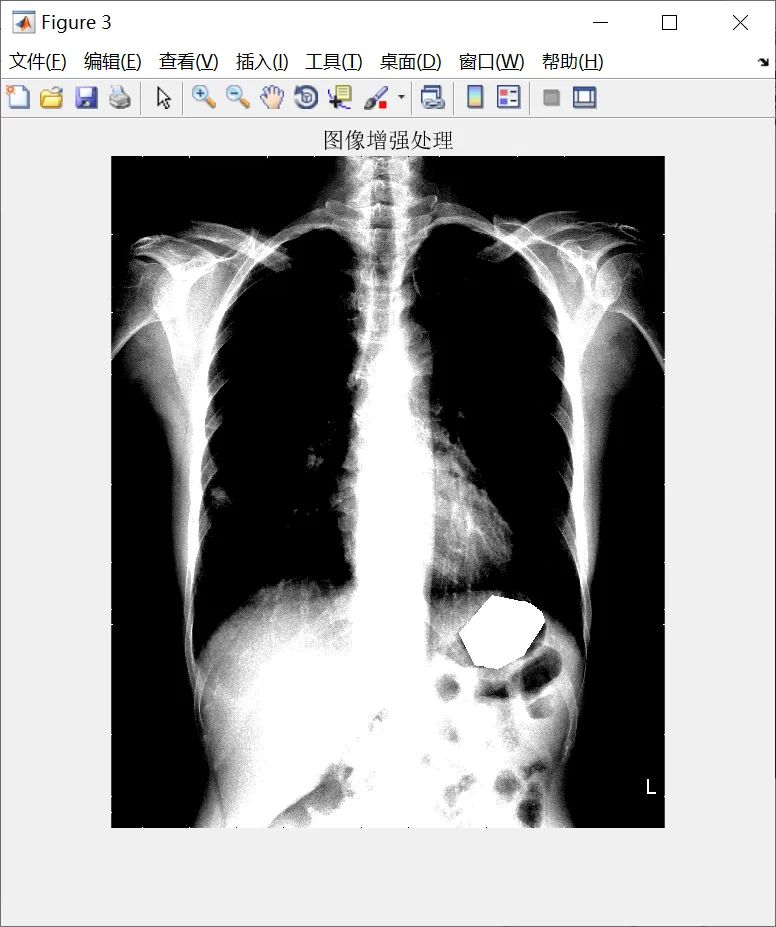

% 图像增强

J = mat2gray(J);

J = imadjust(J, [0.532 0.72], [0 1]);

J = im2uint8(mat2gray(J));

figure; imshow(J, []); title('图像增强处理');